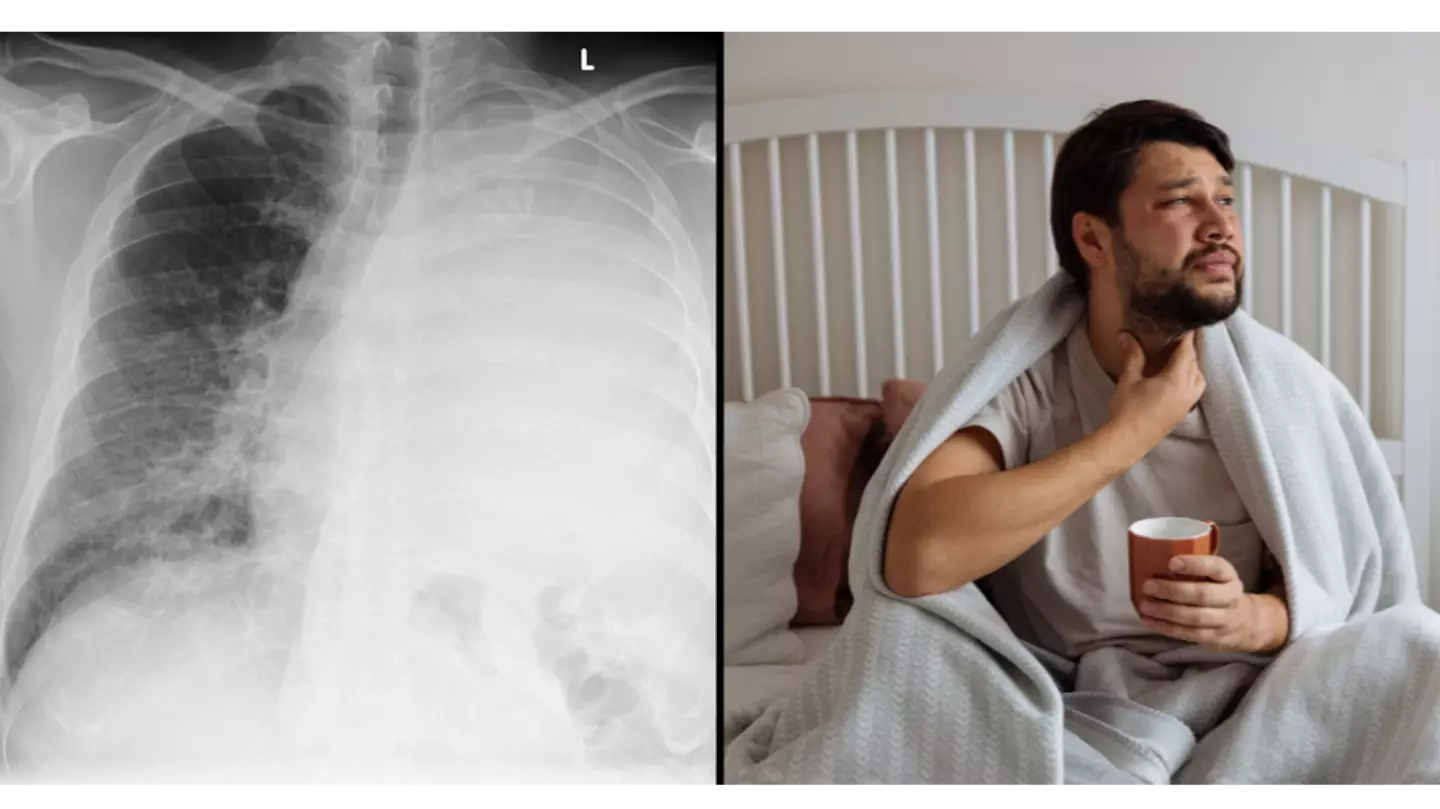

White Lung Syndrome is a type of pneumonia that leads to dangerous inflammation of the lungs that is believed to be caused by a bacterial infection called mycoplasma pneumoniae.

Symptoms of the disease include fever, coughing, fatigue, shortness of breath and the production of green mucus (phlegm).